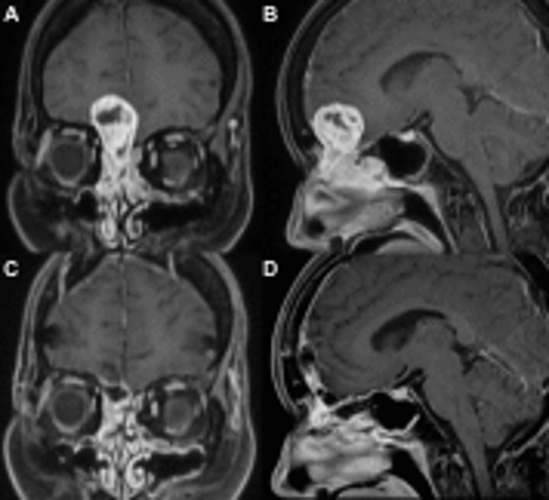

髄膜腫、下垂体腺腫、頭蓋咽頭腫、神経鞘腫に対する手術が可能です。経鼻内視鏡手術が可能です。聴神経腫瘍などの一部の脳腫瘍は新潟大学脳神経外科と連携して、対応しております。

神経膠腫や悪性リンパ腫、転移性脳腫瘍等に対応可能です。